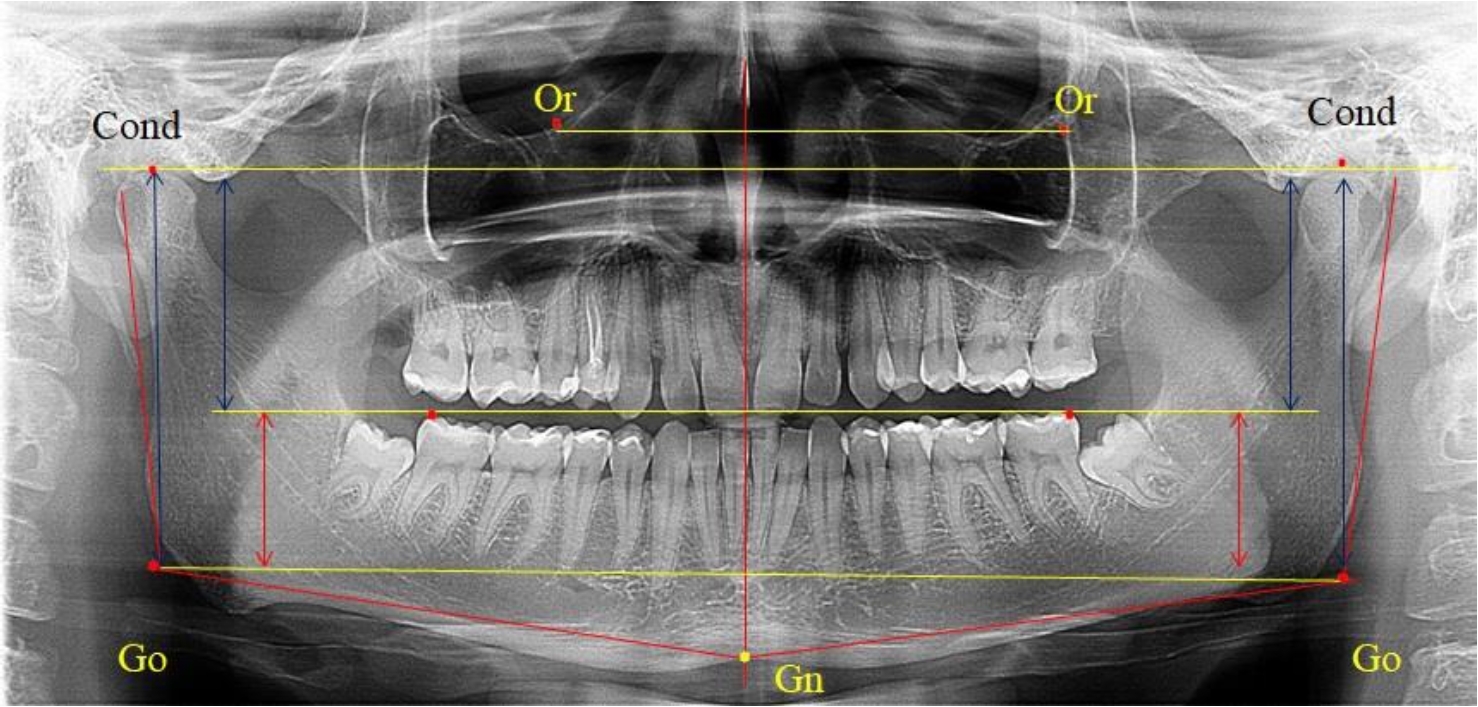

Во 2-ю подгруппу был включен 21 комплект телерентгенограмм и ортопантомограмм [или (28,38 ± 5,24) %], на которых средняя величина отношения верхней части ветви к нижней составляла 1,63 ± 0,03, что было достоверно меньше показателя, полученного по группе в среднем и в 1-й подгруппе.

Визуально параметры ветви отличались от первой группы (рис. 3).

Рис. 3. ОПТГ пациента 2-й группы с уменьшенным коэффициентом соотношения частей ветви нижней челюсти

Высота ветви составляла (62,75 ± 1,42) мм и достоверных различий по этому показателю не отмечено. Максимальная высота была 73 мм, а минимальная – 55 мм. Высота верхней части составляла (38,81 ± 0,76) мм, что было достоверно меньше, чем у людей 1-й подгруппы.

В то же время высота нижнего отдела ветви была (23,94 ± 0,73) мм, и показатель отличался в большую сторону по сравнению с аналогичным размеров в 1-й подгруппе.